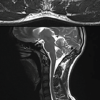

Four months after the initial evaluation, a CT scan revealed a multilobulated, expansile tumor in the humeral head, measuring 5 × 3 cm, with cortical thinning and internal sclerotic septa (Fig. 2). A clinical suspicion of a tumor was raised, prompting the scheduling of an incisional biopsy along with a metastatic bone survey to rule out systemic involvement. The biopsy confirmed the diagnosis of a chondroblastoma in the proximal humerus. In addition, magnetic resonance imaging (MRI) showed a heterogeneous cystic lesion to the humeral head, measuring 4.5 × 4.1 × 5.1 cm. The lesion exhibited thin septations, fluid-fluid levels, and cortical thinning (Fig. 3).